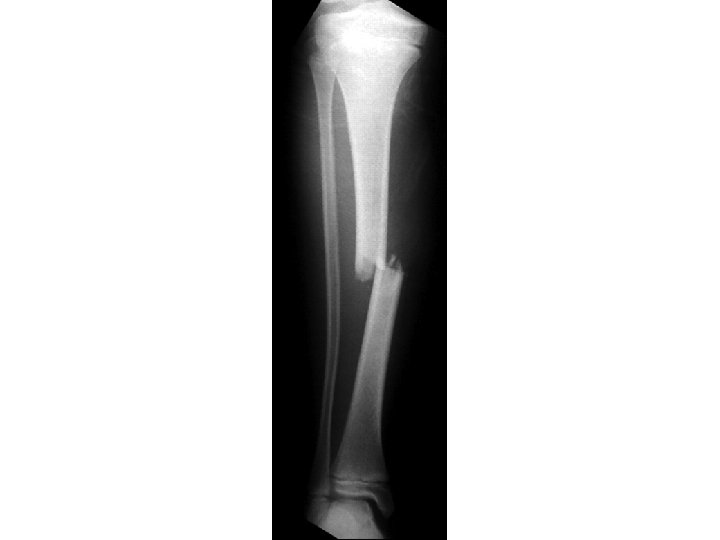

DESCRIBE TO ORTHO ATTENDING…

ANSWER • This one is a bit more challenging! • R midshaft tibia fracture displaced ½ the thickness of the bone without angulation; also there is bayonette appositioning of the fracture fragments • R midshaft fibular fracture with complete displacement and • Also comment if the fracture is open vs closed & neurovascular status